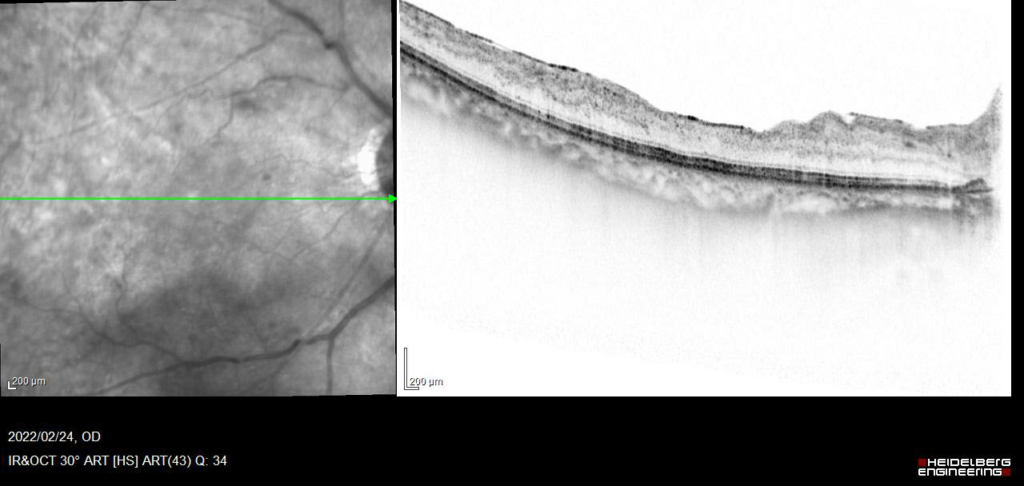

発症後約6か月後

発症後約10か月、抗VGEFの硝子体注射後5Wで黄斑浮腫のみられない状態が維持できるようになった。

現在、経過中。rubeotic glaucoma 血管新生緑内障の発症なし。

視力 右眼 0.09(n.c)